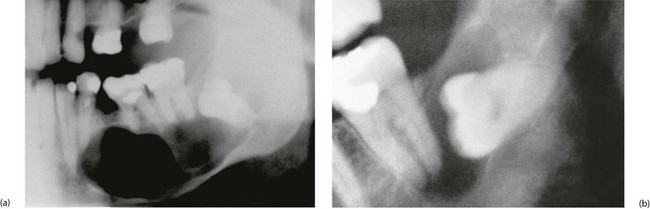

Fig. 48.9 Dental cyst and dentigerous cyst

(a) Large dental cyst in the mandible. This arose from tooth-forming epithelial remnants in the apical area of the lower left second premolar tooth which was extracted several months beforehand due to chronic periapical infection. (b) Dentigerous cyst associated with the crown of an unerupted lower third molar. These cysts originate from epithelial remnants of the tooth bud